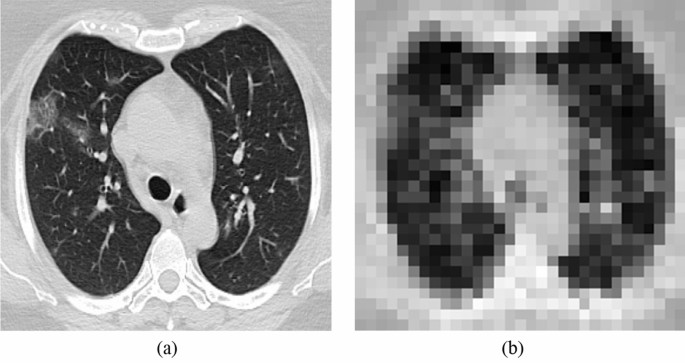

In split learning, the learning process is, as the word suggests, literally split or separated into two parts: the end-systems and the server. Here, the end-systems refer to the multiple hospitals that possess original medical data to be trained in the deep learning model. The server is where the actual learning of the deep neural network occurs. Multiple hospitals are connected to one server; all the hospitals connected to the server collaborate to train the very deep neural network that is placed in the server without exposing their raw data to an external network. A meticulously devised framework of our proposed algorithm is shown in Fig. 1. Every individual hospital only runs the deep neural network up to the first hidden layer. After passing through the first hidden layer, the end-systems send only their feature maps to the server. Since only the encrypted feature map is transferred to the external network, and not the original medical data, the privacy of confidential patient information is preserved. It is coined "multi-site split learning" since multiple hospitals (multi-site) are geometrically spaced apart from each other and the deep neural network is divided among them. In this study, we investigate the performance of our multi-site split learning when changes to the number of end-systems and the data distribution are made. All methods were carried out in accordance with relevant guidelines and regulations. For all experiments, the split learning setup is the same, with the deep neural network being divided amongst the end-systems and one centralized server. Even with the varying number of end-systems that are participating in training the deep neural network, each and every end-system only holds one hidden layer. This hidden layer comprises one convolutional layer. The original medical data, be it the COVID-19 CT chest scans or the MURA bone X-ray images, or the numerical cholesterol data, will pass only through the first hidden layer. The output from the first hidden layer is an encrypted feature map. This feature map is distorted to the point where it cannot be used to inference the original data in this multi-site split learning algorithm. This feature map is the only information that is exposed to an external network—the centralized server. The heavily deformed feature map that is transferred to the server is shown in Figs. 2 and 3. Since only this encrypted parameter is passed to the server, and not the raw medical images, protection of personal information is ensured.

Ensuring privacy of original medical data. Image (a) is the original image of the COVID-19 CT scan. Image (b) shows the highly distorted image after passing through one hidden layer at the hospitals.

The extent to which the raw medical data is protected is shown in the following figures. Figure 2 shows the degree to which the original COVID-19 CT scan is distorted after passing through one hidden layer of each hospital. Figure 2a is the original CT scan of a COVID-19 patient. Figure 2b is the highly deformed image of image (a) after it undergoes the first hidden layer. Each hospital will produce an image like Fig. 2b. All of these feature maps are concatenated and communicated to the server where it then trains the deep neural network.